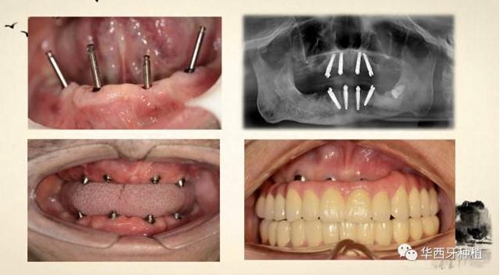

吳教授特別針對手術(shù)難度更大的all-on-four修復(fù)做了詳細的關(guān)于概念、設(shè)計、操作、修復(fù)的描述,首先是針對難度最大的手術(shù)環(huán)節(jié),就解剖、微創(chuàng)操作分別加以闡述。將他自己在臨床工作中的寶貴經(jīng)驗分享給了大家。

對于傳統(tǒng)的all-on-four術(shù)式,吳教授加入了微創(chuàng)的指導(dǎo)思想,設(shè)計時同樣加入數(shù)字化三維重建與修復(fù)一體化設(shè)計,增加了手術(shù)的可控性,同時極大減輕了患者的創(chuàng)傷程度,縮短了修復(fù)周期。

但是,他同時提到了此種修復(fù)方式操作難度要求很高,僅適合有經(jīng)驗的種植醫(yī)生操作。